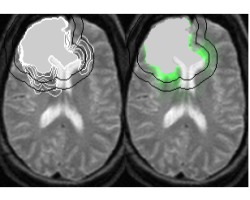

In radiotherapy treatment, the constant margin taken around the visible tumor is a very coarse approximation of the invasion margin of cancerous cells. This work tries to solve the problem of adapting the radiotherapy regions to the tumor growth dynamics. The method proposes approximate invasion margins of the tumor based on its growth dynamics. Determining radiotherapy regions based on these invasion margins would increase the effectiveness of the treatment. The low density tumor parts, undetectable by the current imaging techniques, are extrapolated in a magnetic resonance image (MRI). The extrapolation takes into account the underlying tissue structure (grey matter, white matter, fiber directions), the tumor growth dynamics approximated by the Fisher-Kolmogorov model and the segmented tumor in the image.

We propose a bio-mechanical approach based on a finite element model (FEM) of the brain to model this deformation. It takes into account the patient specificity and anatomical cerebral structures to predict the brain deformation.

This study is based on the analysis of 7 cases of Parkinson operations, realized at La Pitie Salpetriere hospital (Paris). It focuses on modeling the static effects of gravity on the brain deformation after dura-mater opening, visible on the post-operative MRI.